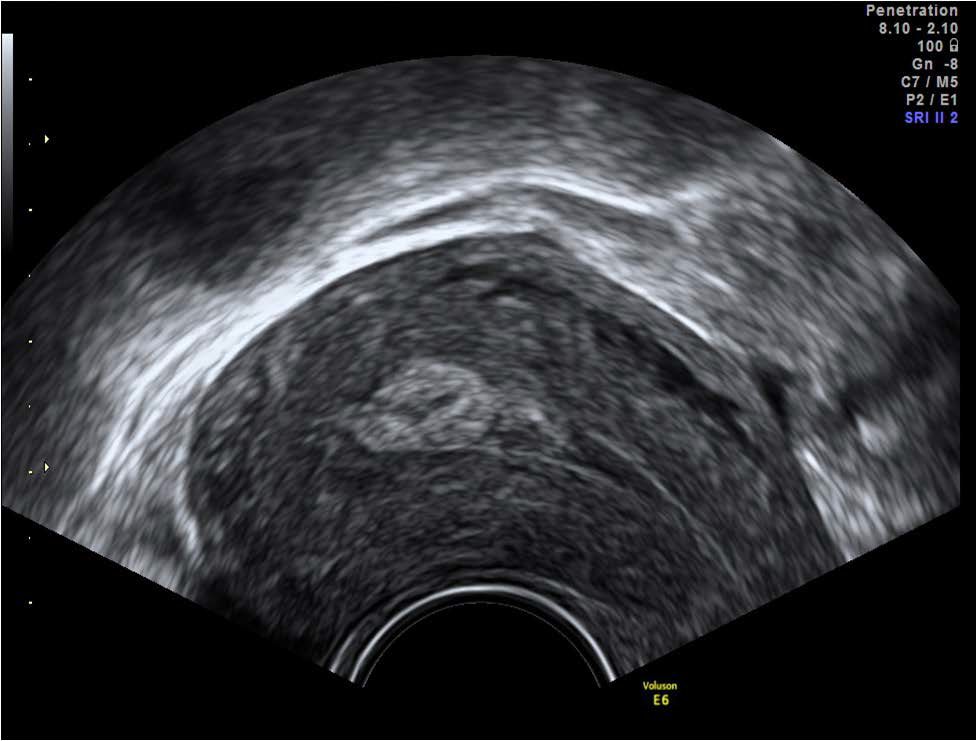

Figure 5: Echogenic mass within the endometrial cavity seen in the sagittal plane on transvaginal scan 6 weeks post vaginal delivery.

figure 5